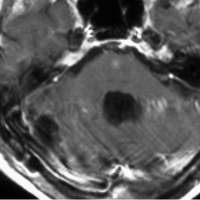

フォン・ヒッペル・リンドウ病の患者さんの脊髄(胸髄)にできた血管芽腫です。上下の脊髄が腫れたり,脊髄の中に空洞(腫瘍のう胞あるいは脊髄空洞症といいます)ができます。 手術治療は症状が出るまで,あるいは症状がかなり強くなってからしかしません。なぜなら,たくさんできる(多発)することが多くて,複数回の手術になってしまうこともあるからです。手術をするたびに,四肢のしびれや麻痺などの後遺症がのこる可能性もあるので,この手術は,脊髄腫瘍の手術経験が相当にたくさんある脳外科医にしかできません。